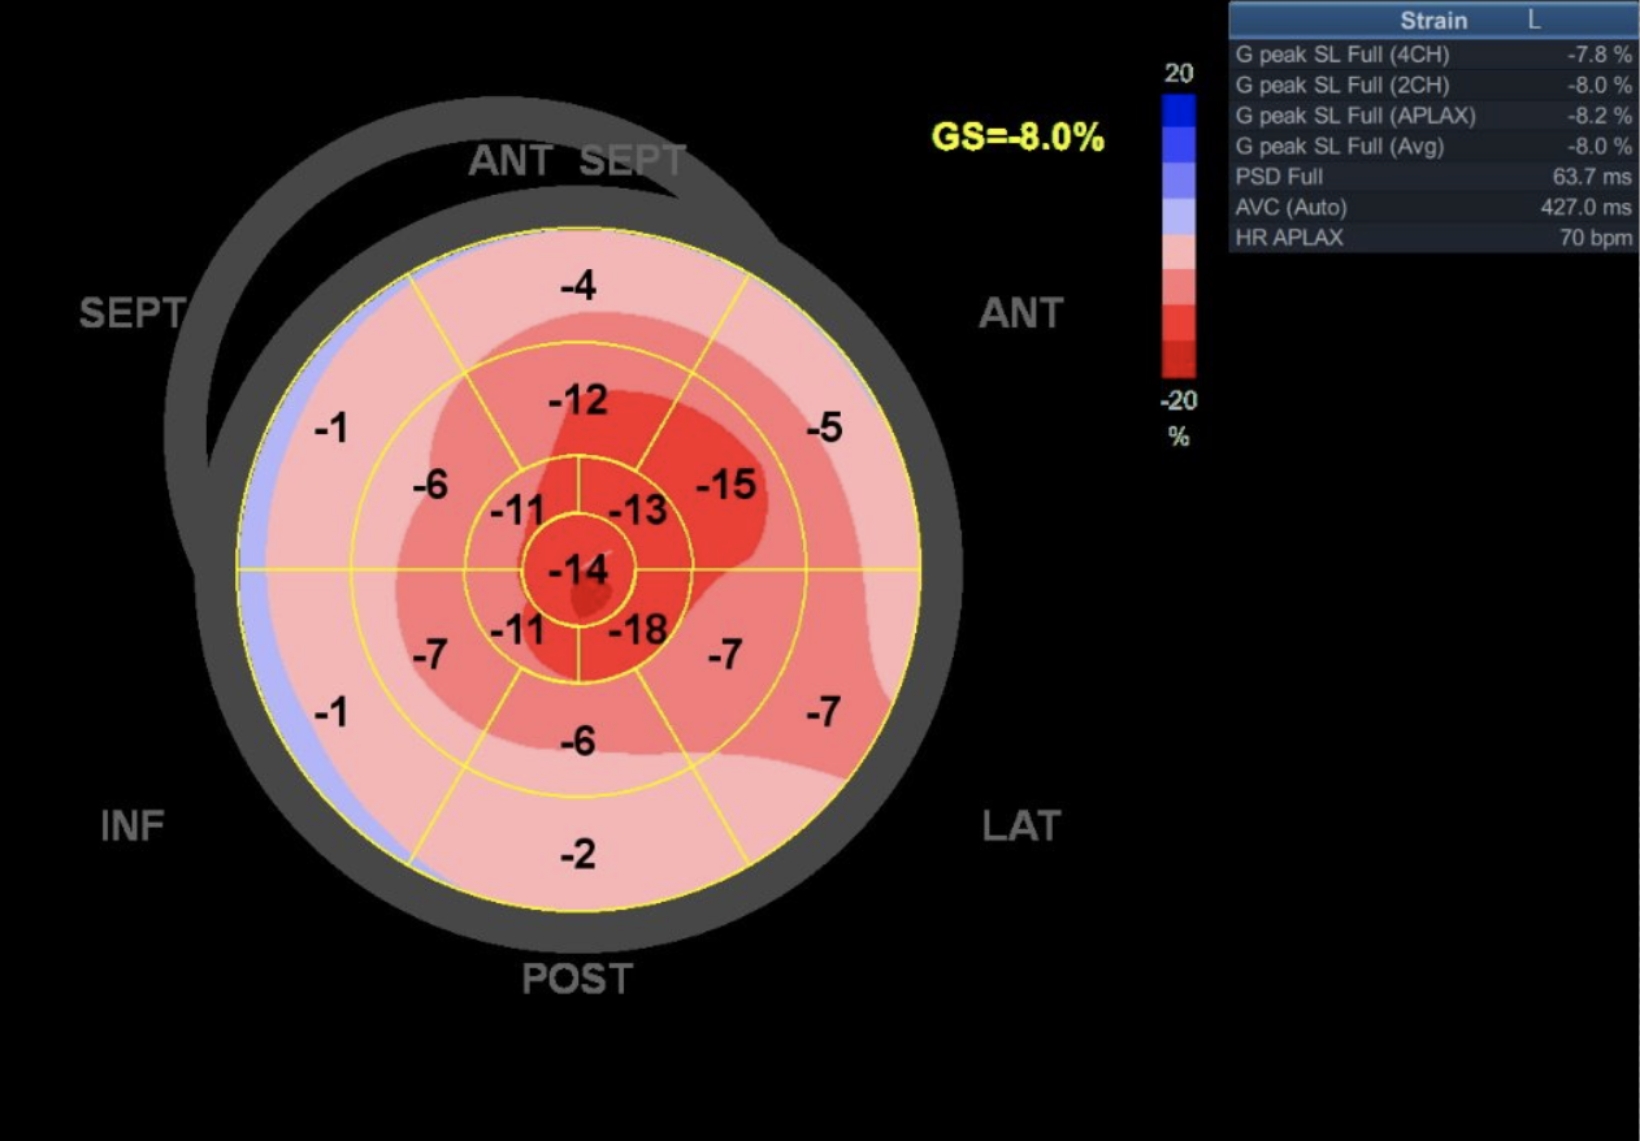

Voici ce que votre confrère a indiqué dans son rapport :

- Mouvement longitudinal anormal, cinétique anormale du VG

- Faible strain longitudinal global (norme < -16%)

- Diminution en valeur absolue du strain, plus marquée au niveau du segment moyen et de la base en comparaison à l’apex

Apex

Réponse

Le plot révèle une représentation en œil de bœuf typique d'une amylose :

- Faible strain longitudinal global (norme < -16%)

- Diminution en valeur absolue du strain, plus marquée au niveau du segment moyen et de la base en comparaison à l’apex